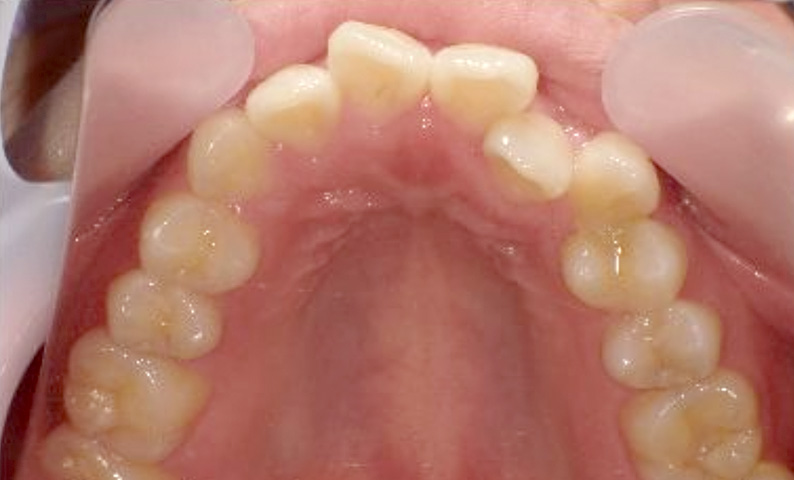

症例_024 上顎だけの部分矯正

治療期間:7ヶ月金額:30万円+税女性前歯のガタガタ上の前歯だけ

| Before | After |

|---|---|

|